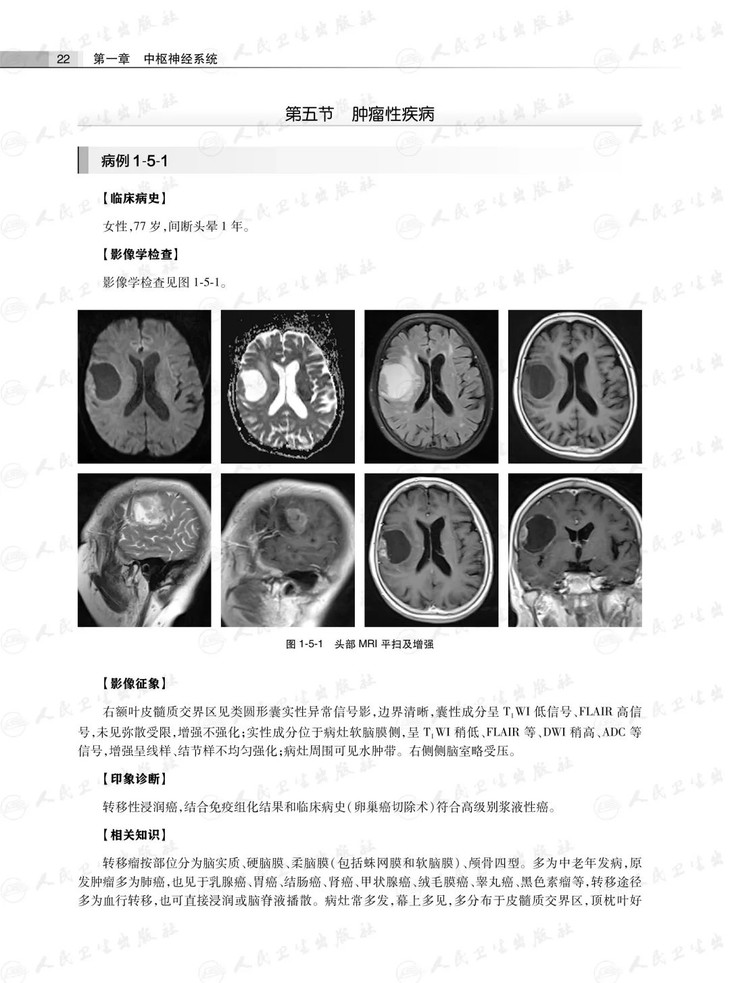

样章试读